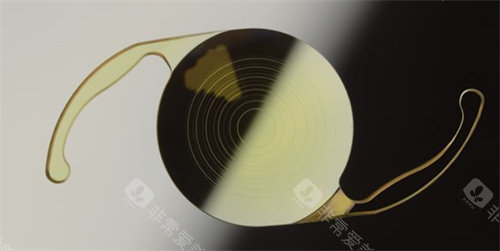

ICL晶体植入手术作为高度近视矫正的主流方案,凭借其可逆性、不损伤角膜的特点,成为越来越多近视患者的选择。

不损伤角膜:适合角膜薄、干眼症等激光手术禁忌人群。

可逆性强:晶体可随时取出,不影响未来其他治疗。